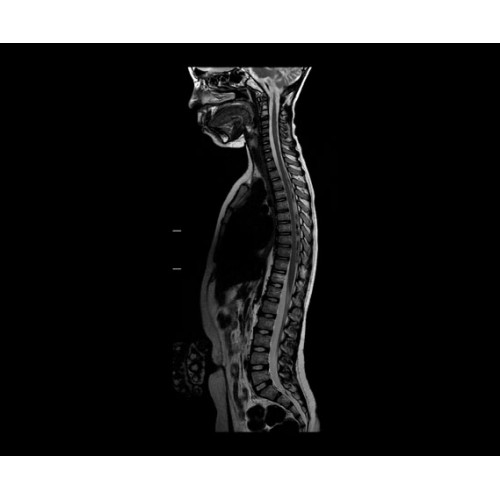

В систему SIGNA PET/MR встроены запатентованные детекторы кремниевого фотоумножителя (SiPM) и сверхчувствительные кристаллические сцинтилляторы на основе лютеция толщиной 25 мм. Благодаря этому обеспечивается исключительная чувствительность и возможность использования времяпролетной диагностики (TOF).

Кроме того, в результате использования технологии TOF и инновационной технологии реконструкции Q.Clear вы сможете добиться прекрасного соотношения сигнал/шум. А благодаря технологии нулевого времени эхо (ZTE) визуализировать костную структуру без ионизирующего излучения. Все эти разработки для улучшения качества сканирования и точности анализа помогут вам использовать весь потенциал ПЭТ/МРТ.

• МРТ с функцией нулевого времени эхо (ZTE) отличается точностью, возможностью персональных настроек и отсутствием ионизирующего излучения. Она приходит на смену традиционному исследованию на основе рентгеновского излучения. МРТ с функцией нулевого времени эхо (ZTE) на базе SIGNA ПЭТ/МРТ является более надежной и быстрой по сравнению с системами, использующими сверхмалое время эхо (UTE).